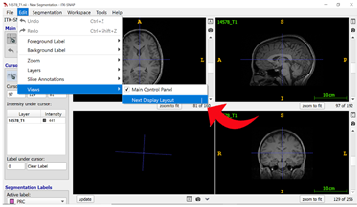

Step 3: Switching Between Views Since segmentation is done primarily on the coronal view of the T2-weighted image, you can easily switch between views using the shortcut SHIFT + | or by clicking “Edit” in the top ribbon and then “Views” in the dropdown menu to select “Next Display Layout” (see 6.1 ITK-Snap Shortcuts for more information).